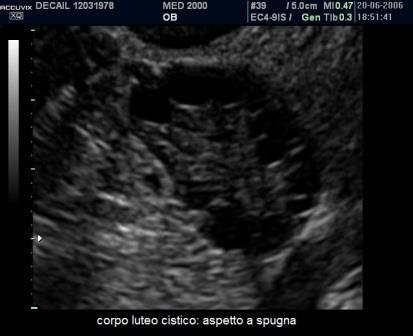

Il corpo luteo cistico può avere dimensioni variabili ( 3 - 10 cm.) ed aspetti diversi legati sia alla quantità di sangue presente nella cisti sia alla quantità di sangue coagulato presente. Nelle fasi di sviluppo della formazione cistica e dello stravaso di sangue all'interno della cisti possono aversi aspetti ecografici vari e caratteristici:

- aspetto a spugna o "sponge like" per la presenza di sangue coagulato, con aspetto di fini trabecolature iperecogene, che occupa gran parte della cisti; il power-Doppler mostra assenza di vasi ematici all'interno della cavità cistica;